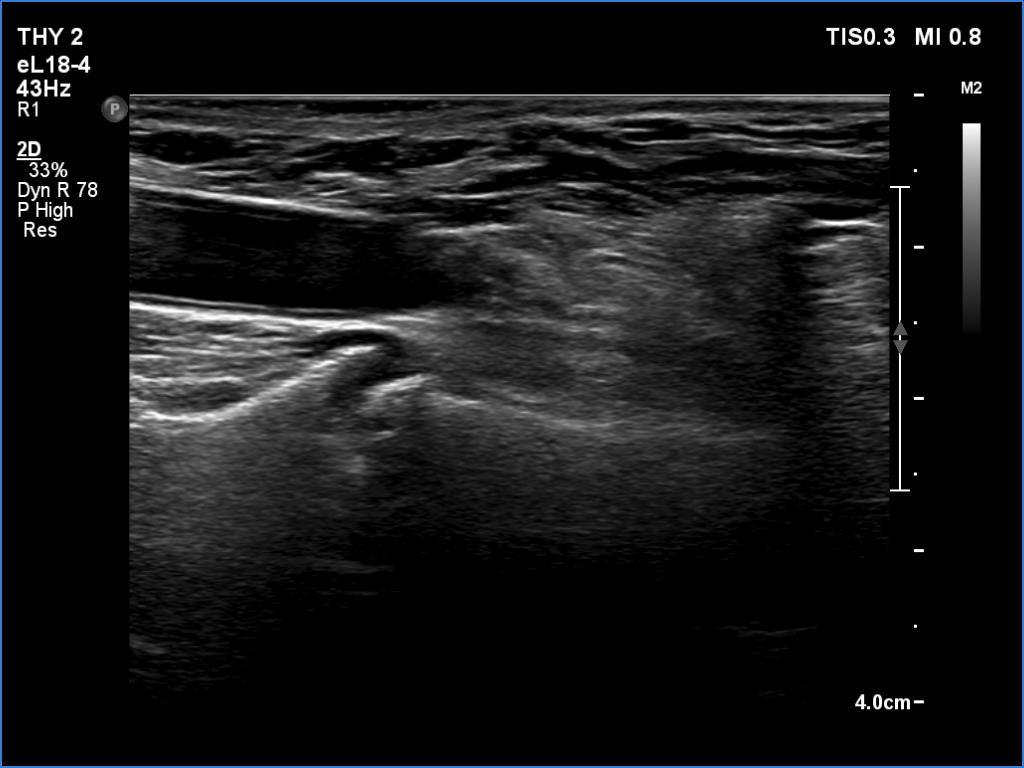

The operated thyroid - case 169

Follow-up investigation 6 months after first visit (ultrasonographic picture 2)

Right lobe, longitudinal scan. Connective tissue replaces the removed thyroid.